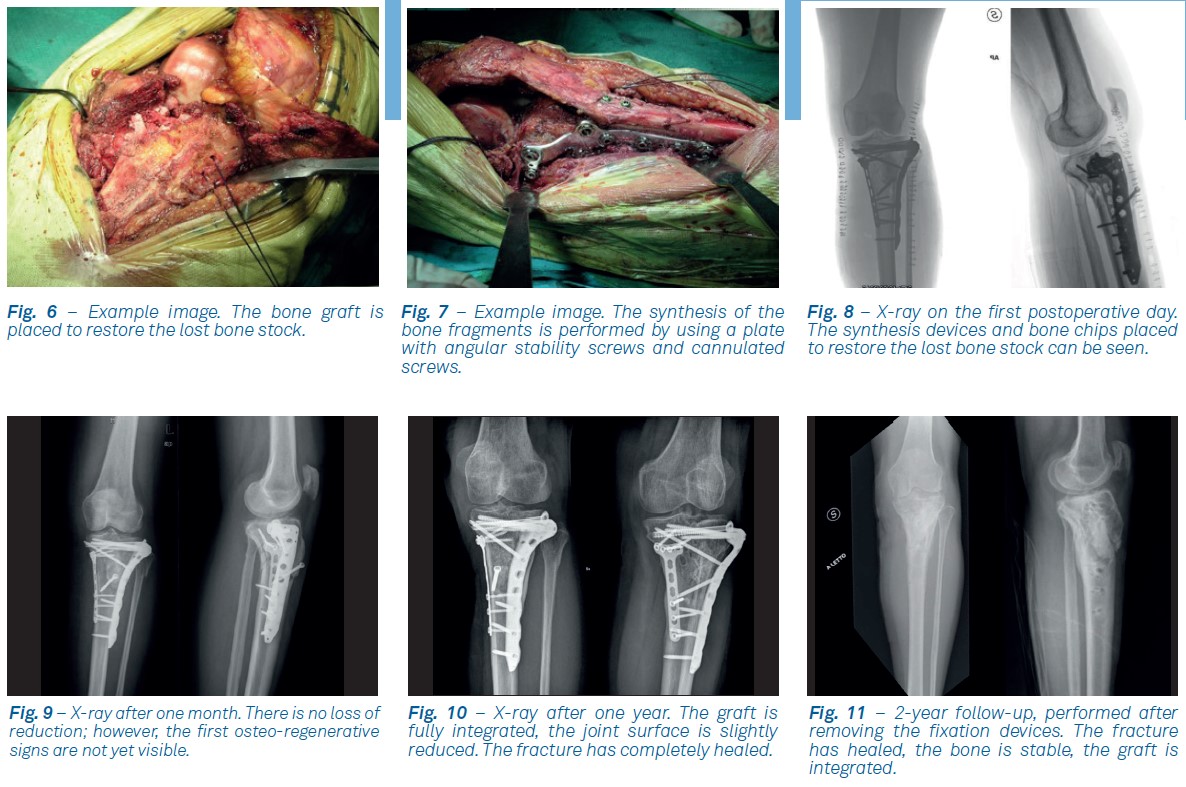

The patient came to the emergency room following a road accident. A displaced tibial plateau fracture was clinically diagnosed. The X-ray examination showed the need to treat it surgically. Firstly, reduction of the medial tibial plateau fracture was performed by fixating it with a T-plate, once the medial column was stabilized, the articular surface of the lateral plateau was reduced and it was provisionally stabilized with Kirschner wires and cannulated screw. The metaphyseal region of the lateral tibial plateau was then reduced, and the metaphysis was reconstructed by restoring the lost bone stock through the use of equine derived enzymatically deantigenated bone blocks which were crushed into chips for easier filling of the tissue gap.